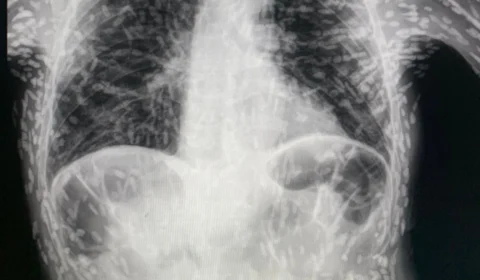

Médico divulga raio-x de paciente com tórax cheio de ‘ovos de verme’

Médico compartilha radiografia de paciente com doença parasitária no pulmão após tosse persistente